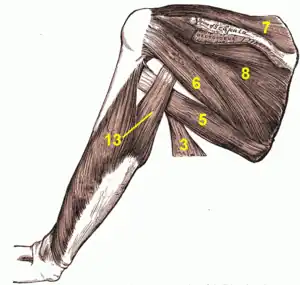

3. correspond au muscle grand dorsal

5. correspond au muscle grand rond

6. correspond au muscle petit rond

7. correspond au muscle supra-épineux

8. correspond au muscle infra-épineux

Le complexe articulaire de l'épaule met en relation douze muscles principaux :

- le muscle subscapulaire (ou sub-scapularis) ;

- le muscle supra-épineux (ou supra-spinatus) no 7 ;

- le muscle infra-épineux (ou infra-spinatus) no 8 ;

- le muscle petit rond (ou teres minor) no 6 ;

- le muscle grand rond (ou teres major) no 5 ;

Remarque : le grand rond n'est pas considéré comme faisant partie des muscles de la coiffe des rotateurs. - le muscle rhomboïde ;

- le muscle grand dorsal no 3.